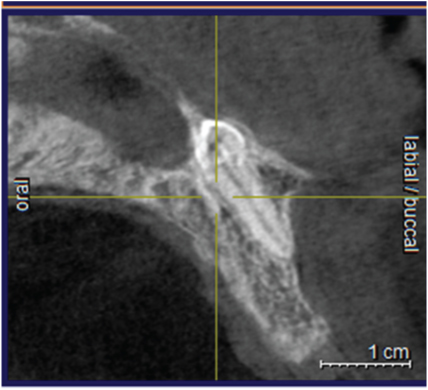

A 25-year-old male reported to the dental clinic with a chief complaint of mobility in the upper front teeth following trauma. On clinical examination, the upper anterior teeth were proclined with grade-III mobility in 11 and grade-II mobility in 12, 21, 22. Orthopantomogram (OPG) revealed bone loss upto the apical third in the upper anterior teeth. Additionally, radio-opacity was seen in the anterior nasal spine which was missed as an artefact [Table/Fig-1]. The anterior teeth were planned for extraction followed by implant placement for which a Cone Beam Computerised Tomogram (CBCT) was taken which showed the panaromic [Table/Fig-2], images of the anterior nasal spine. An inverted tooth like structure was seen in the 3D image. The cross sectional image confirmed the radio-opacity to be a tooth since the enamel, dentin and the pulp were clearly distinguished [Table/Fig-3,4 and 5].

Cross Sectional View which justifies the radio-opacity to be a tooth since the enamel, dentin and pulp structure of the tooth is clearly differentiated